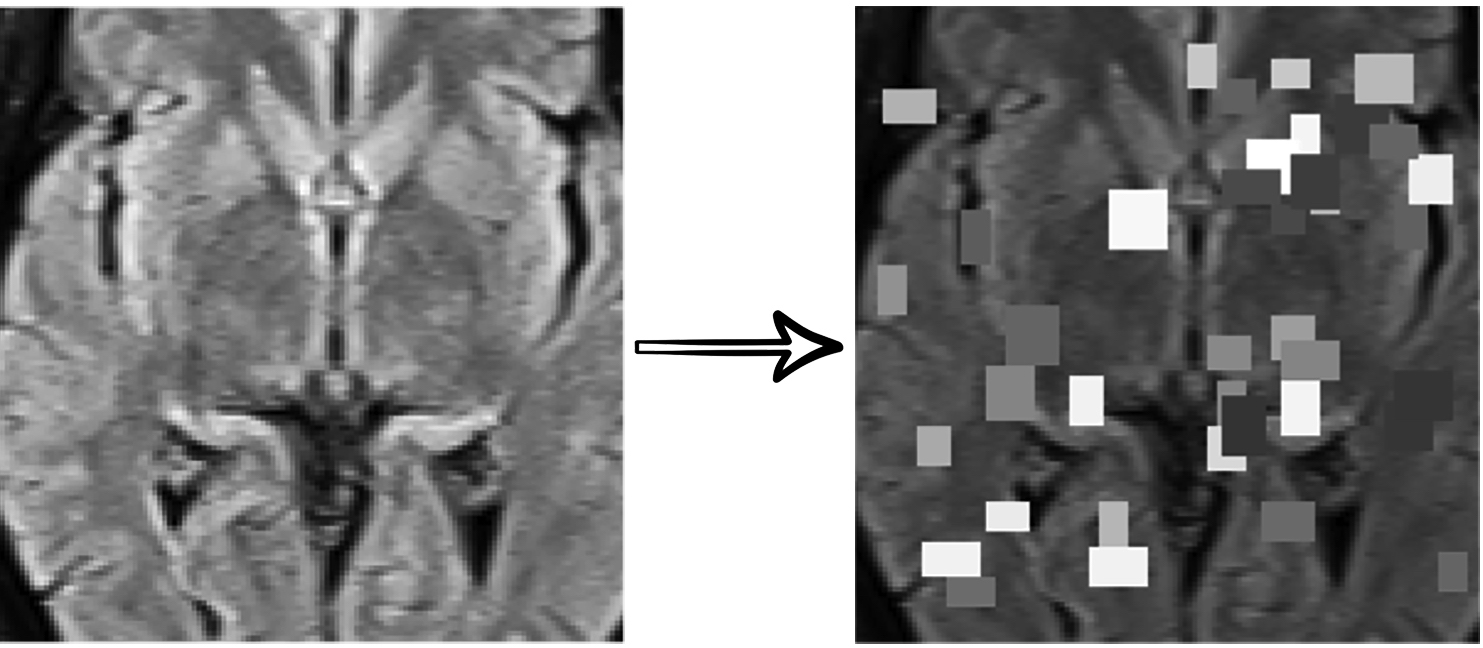

This process is conducted during each step, and the former output image is passed as the input image of the latter (Fig. 2). It is notable that since this method is performed on each image separately, it can adapt to images with different grayscale distributions. This enables us to segment white matter lesions in all patients regardless of the patient positioning and the device setting.

As it is mentioned earlier, the classification task is mainly based on a specific type of white matter lesions. Hence, the CNN model, which can successfully classify patients based on the aforementioned biomarker, should mostly attend to the areas of the input image containing white matter lesions. Consequently, we designed a component for white matter lesion segmentation to be performed on the given MR images. This component is comprised of three steps:

Segmenting bright areas of the brain image, which is mainly consisted of white matter lesions (if any)

For each step, we perform adaptive thresholding based on the Otsu’s threshold selection method [23]. In each stage, the objective is to find the value of pixel intensity at which the between-class variance is maximized. This threshold value, , divides the input image pixels into two groups and :